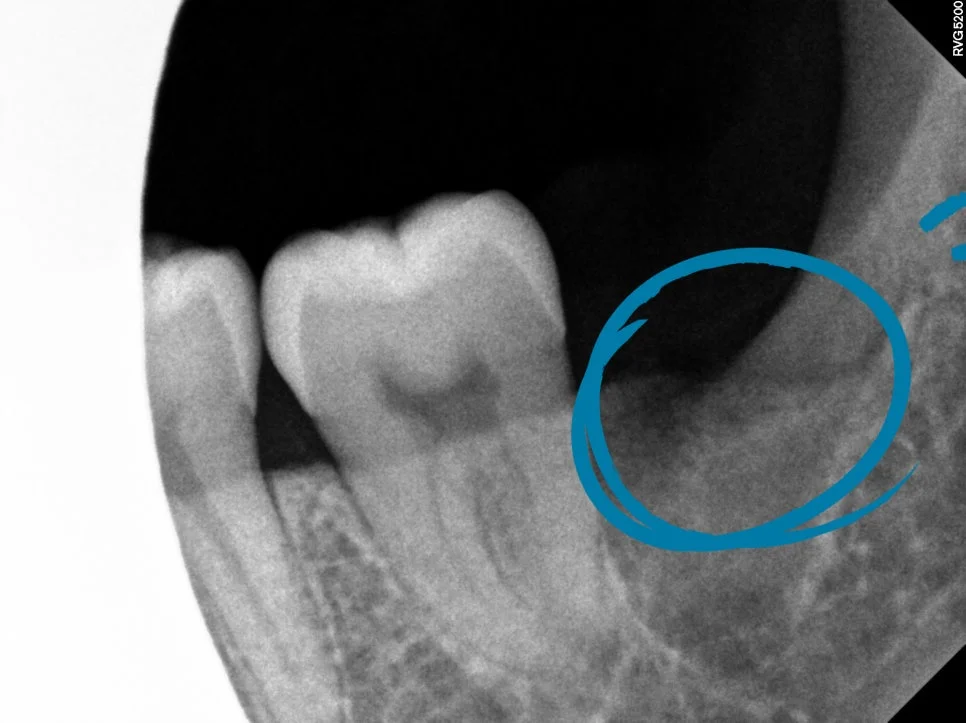

파노라마 X-ray — 발치 전 전체 확인

파노라마 X-ray — 상하 양쪽 사랑니 4개 위치 (파란 화살표)

발치 결과 — 하악 양쪽 (제2대구치 보존 확인)

무엇보다 제2대구치 역시 손상 없이 잘 보존되었습니다. 이 부분이 가장 중요한 체크포인트였죠.

잔여 뿌리 없이야 발치가 잘 되었다고 볼 수 있습니다.

이런 사후 X-ray는 수술이 정확하게 끝났는지 검증하는 핵심 자료라 꼭 확인해야 하는 단계이기도 합니다~